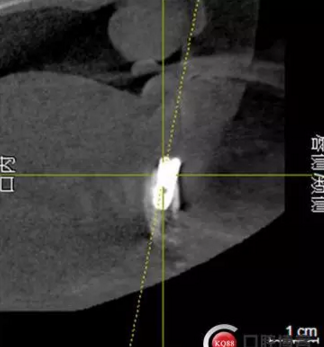

檢查:上頜無(wú)牙頜假牙穩(wěn)定性尚可,下頜3435364243殘根;33殘冠1-2度松動(dòng),其他牙齒缺失;CBCT檢查:下頜牙槽骨前牙區(qū)骨高度足,后牙區(qū)骨高度最低為8mm,骨寬度足。

2)術(shù)前準(zhǔn)備及手術(shù)過(guò)程,測(cè)量血壓及血糖,簽種植知情同意書;嚴(yán)格遵循無(wú)菌操作,局麻下采用微創(chuàng)技術(shù)于323436分別植入osstem4.0X10,4.0X10,4.5X7; 434446分別植入osstem4.0X1O,4.0X10,4.5X7.初期穩(wěn)定性均達(dá)到了35N.CM以上;嚴(yán)密縫合,止血,種植體位點(diǎn)和方向與設(shè)計(jì)一致。